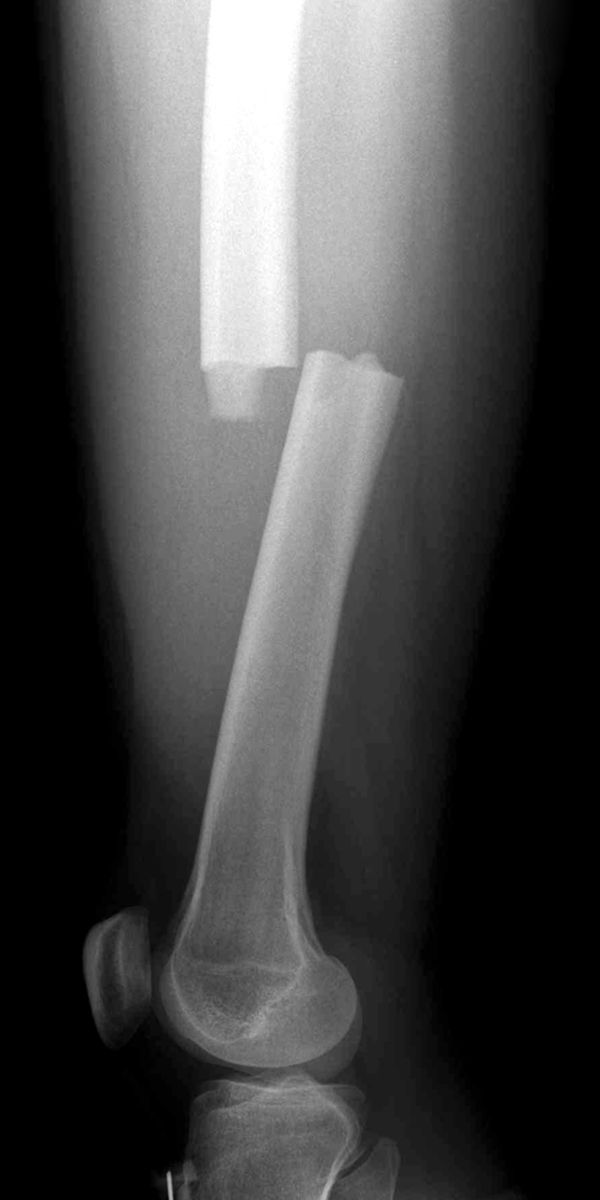

Radiografías. La forma más frecuente de evaluar una fractura es mediante una radiografía, que ofrece imágenes claras del hueso. Las radiografías pueden mostrar si un hueso está intacto o roto. También pueden mostrar el tipo de fractura y dónde se encuentra dentro del fémur.

Una radiografía muestra una fractura transversal del fémur. La ruptura se produce en una línea recta horizontal que atraviesa la diáfisis.

Reproducido desde JF Sarwak (ed): Essentials of Musculoskeletal Care, ed 4. Rosemont, IL. American Academy of Orthopaedic Surgeons, 2010